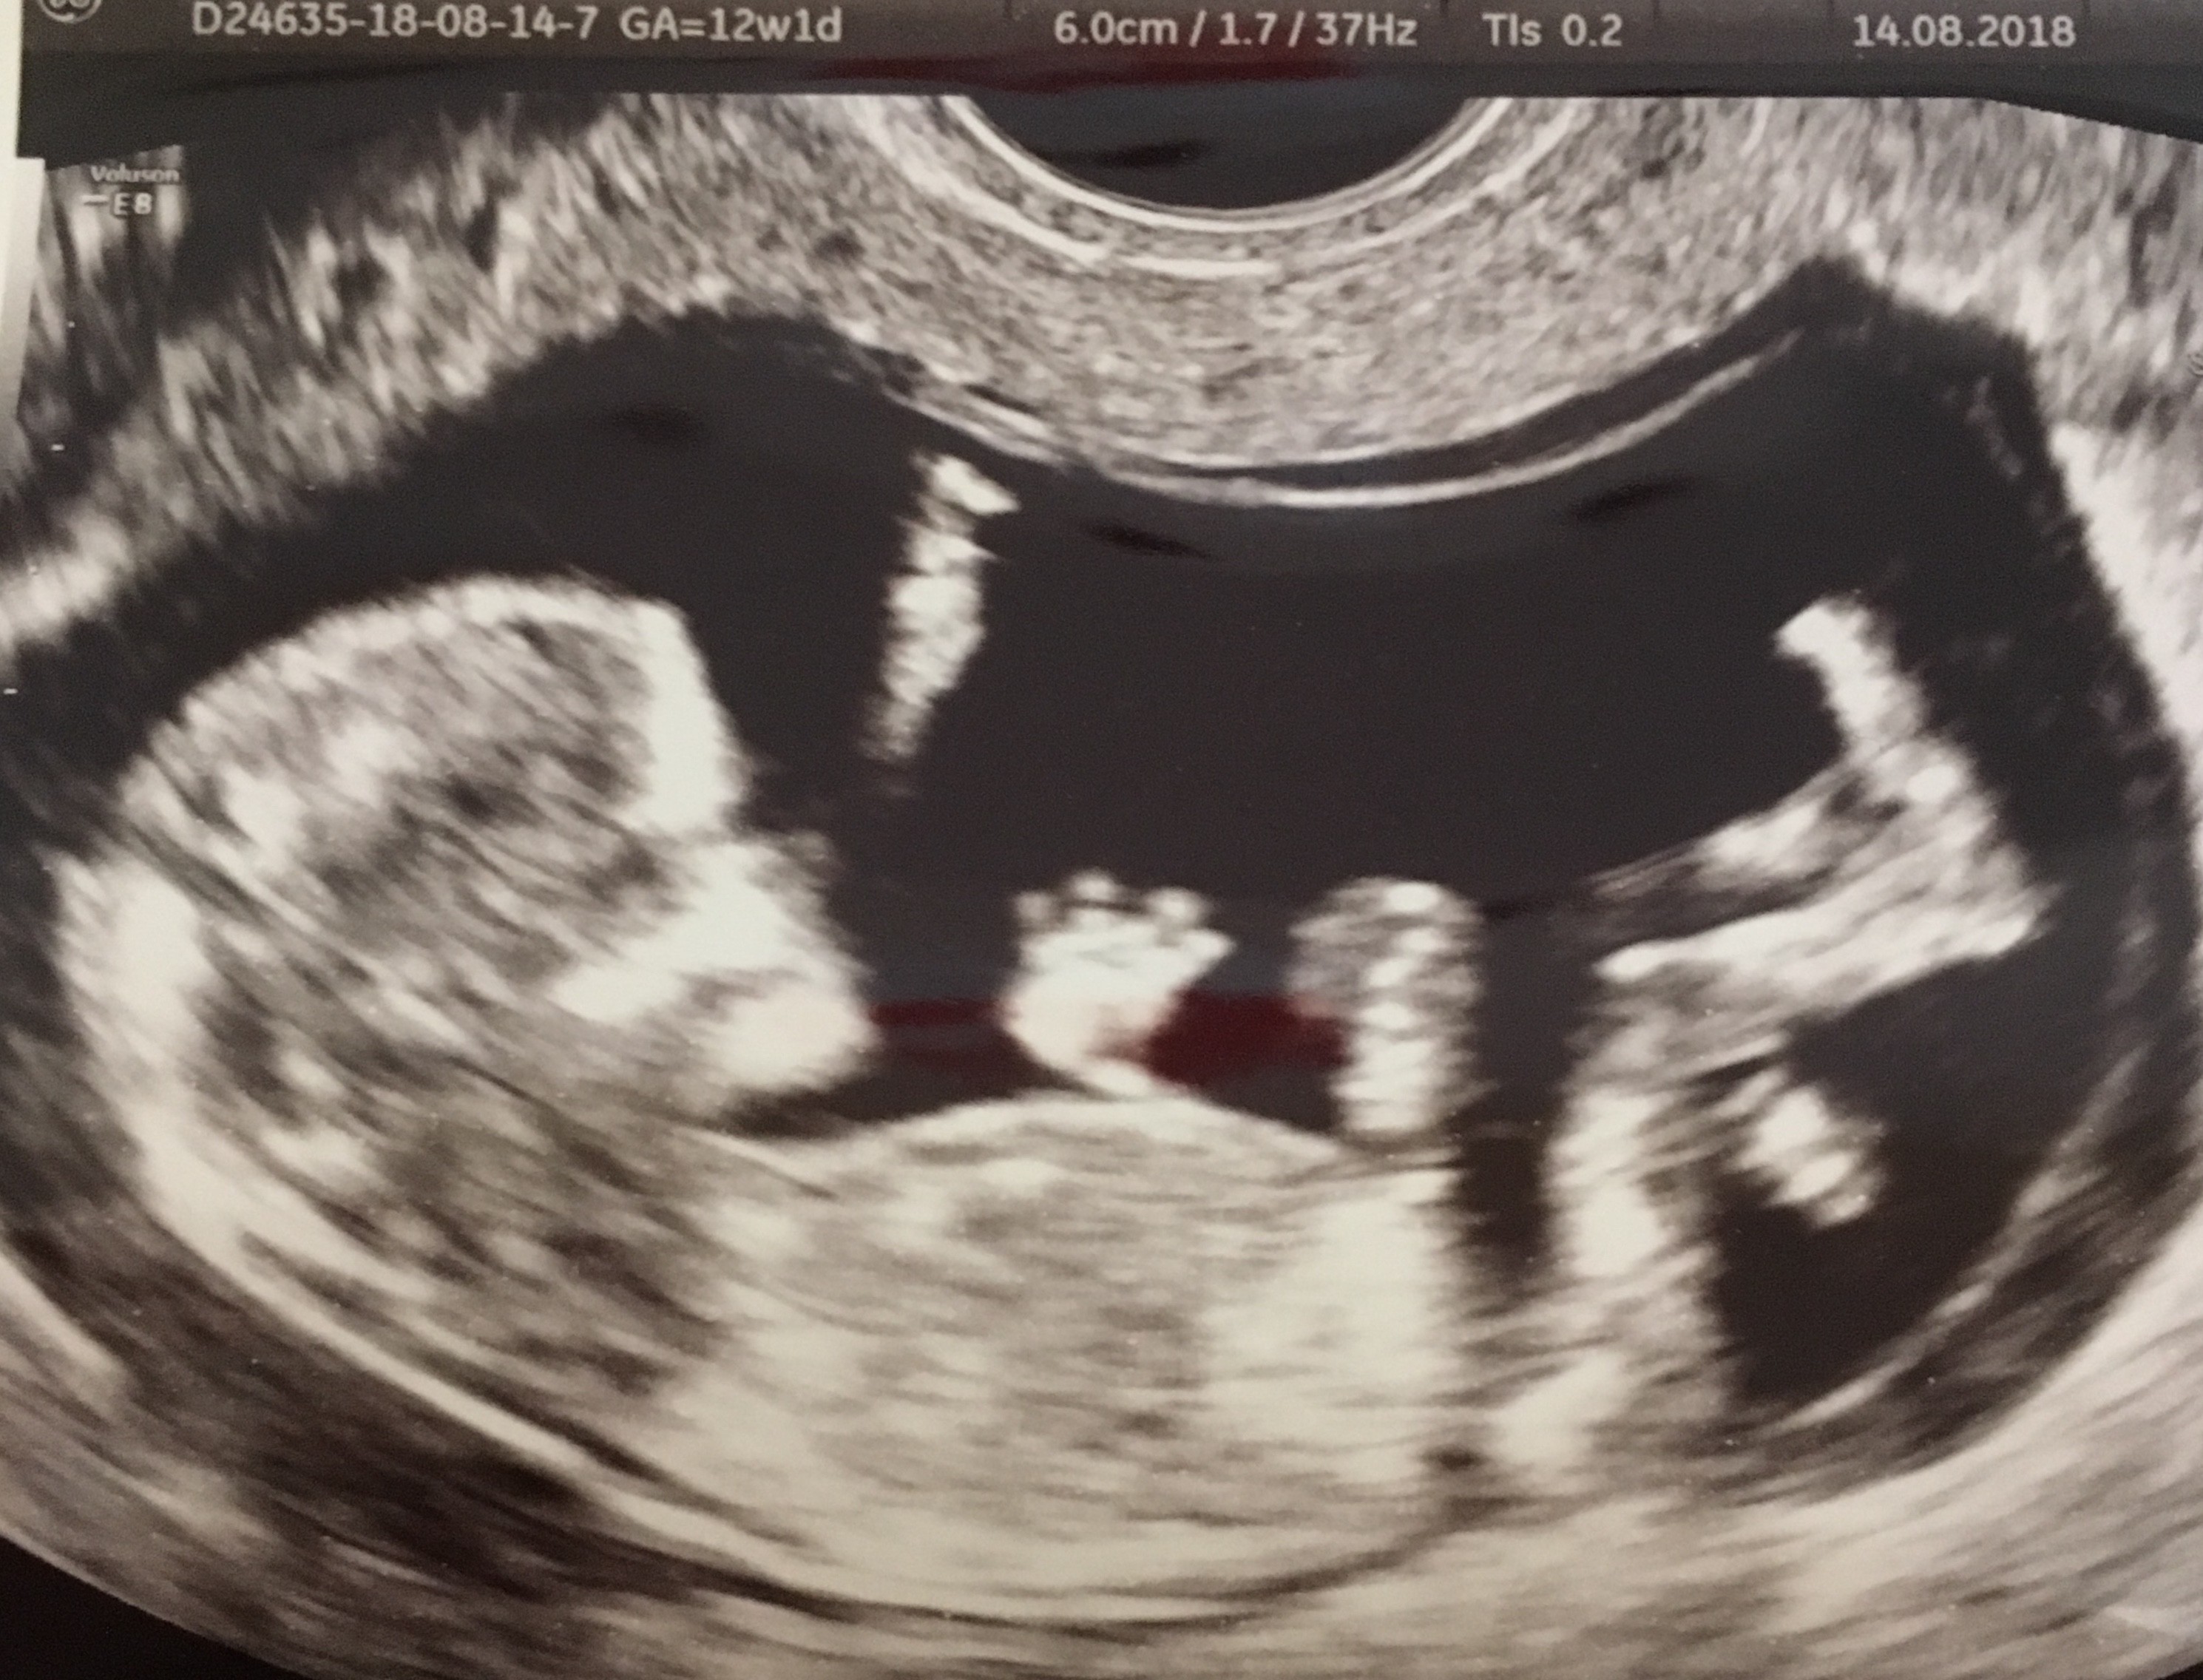

5,98 cm szczescia. Nosek jest, przezierność ok, 2 rączki, 2 nóżki, 2 półkóle mózgowe (zaczątki), serduszko 170, żołądek, pęcherz moczowy, kręgosłup, przepływy żylne - ok. Na usg wszystko w porządku.

Krasnal spał..... jak mi gin zaczął stukać w brzuch to się wystraszyłam, ze serduszko przestało bić. A on mówi: „spi i nie współpracuje”..... Kaszlałam i nic. Po ilus puknieciach obudził się. Czekam na oddanie krwi. Wynik pappa za tydzień. Nifty za 9 dni roboczych.

Jest 12+1, wyglada na 12+3.

Szyjka 3,16. Krwiaków nie widać.